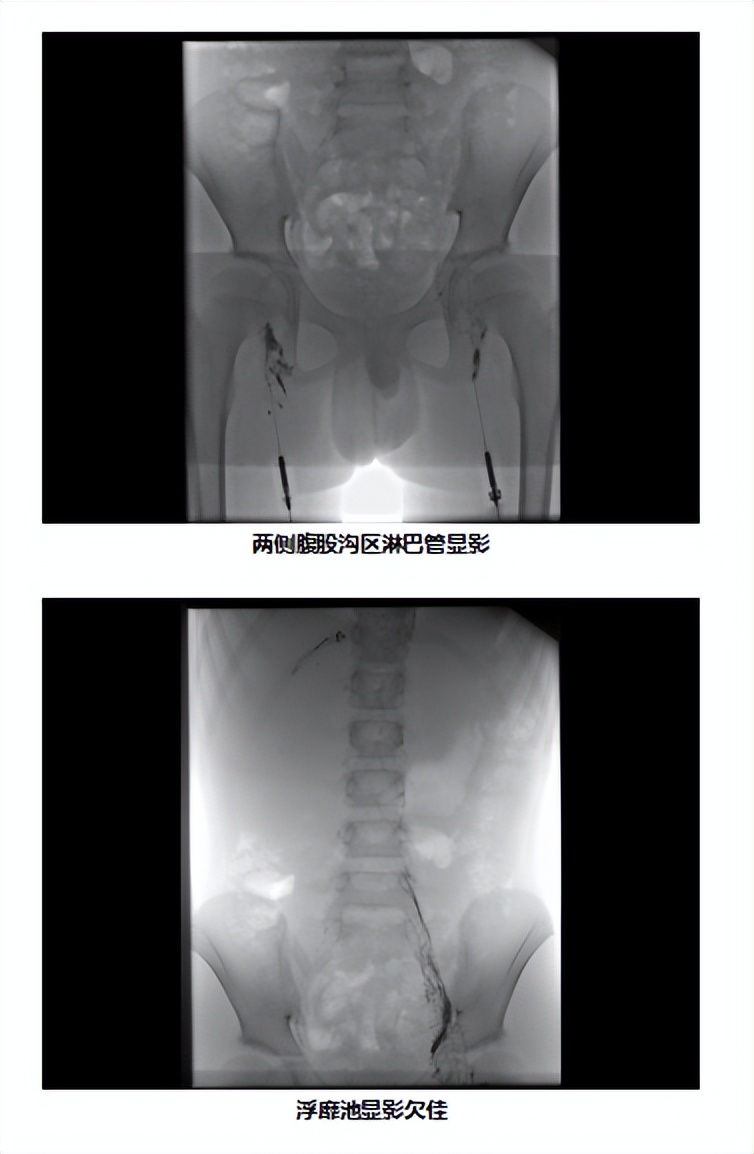

二、手术过程

在安排的手术时间,家长如约住院,顺利完成术前准备,手术当天,患儿在全麻的过程中完成了手术,耗时3小时,应用穿刺针行淋巴结穿刺,注入碘油。显示:右上纵隔淋巴管及右颈静脉角胸导管右位引流,扩张伴出口流出不畅。右侧胸腔积液,T10-12水平右肋间淋巴管造影及返流。术后孩子也没有任何不适,身上也没有任何伤疤。共住院7天,患儿平稳出院。